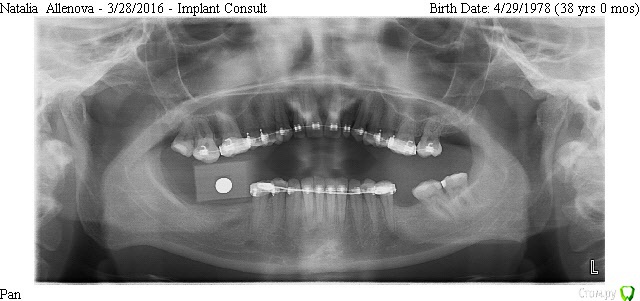

Natalia105 Опубликовано 6 апреля, 2017 Поделиться Опубликовано 6 апреля, 2017 Здравствуйте уважаемые врачи. У меня установлены три импланта в июне 2016 года - на зубы 19, 30 и 31, прижились хорошо. При попытке установки коронок выяснилось, что коронки слишком маленького размера (импланты 30 и 31 стоят слишком близко друг к другу и нет достаточно места чтобы сделать коронки крупнее). Между десной и коронками в глаза бросается металл. Выглядит все это ужасно некрасиво и неестественно. Доктор уверяет меня, что красота в молярах это не главное, а главное это функциональность. Но разве одно с другим несовместимо? Тем более за такие деньги... Да и маленькие коронки тоже ведь снижают функциональность. Коронки сделали только в марте, потому что ждали снятия брекетов. Я пока отказалась от установки таких коронок до выяснения следующих вопросов: 1. Размеры коронок 30 и 31 зубов слишком маленькие, так как недостаточно места. Импланты стоят слишком близко друг к другу, что это - ошибка доктора? Он делал операцию "на глазок" без шаблона (возможно потому, что у меня в тот момент были брекеты). На мои претензии доктор ответил, что кость в том месте мягкая и он не мог поставить 31 имплант дальше. Хотя другой доктор до этого говорил, что с костью у меня там все в порядке (я делала 3D рентген)... Но ведь если кость там действительно мягкая - доктор должен был нарастить ее, не так ли? Потом поставить туда широкий имплант + индивидуальный абатмент, и в итоге коронку нормального размера (это ведь моляр). Так ведь, или я ошибаюсь? 2. В моей ситуации (если не удалять импланты) можно и нужно ли сделать на 31 зуб широкий индивидуальный абатмент и более длинную коронку? При этом с нормальной нагрузкой на имплант (чтобы не расшатался) и чтобы коронка не сломалась под нагрузкой? Или как вариант - одну большую длинную коронку на два импланта? 3. На рентгене видно, что импланты 30 и 31 недостаточно покрыты костью - нужно ли нарастить кость? Или и так сойдет? Если оставить так - не будет ли рецессия кости и не приведет ли в скором времени к потере импланта? 4. Между десной и коронками в глаза бросается металл. Доктор уверял меня, что наращивать десну мне не нужно, потому что там будут скапливаться бактерии (между коронкой и десной), что приведет к воспалению десны и другим неприятным последствиям. Так ли это? Но ведь если десну не нарастить, то на торчащий абатмент будет наматываться еда (особенно мясо) - что тоже неприятно и возможно больно. Да и выглядит неэстэтично... Что же мне делать - наращивать десну или нет? 5. Если оставить 30 и 31 коронки такими маленькими, то имеет ли смысл тогда сделать еще один имплант на 32-й зуб? Во-первых, чтобы продлить зубной ряд - жевательная способность улучшится, во-вторых, нагрузка на 30 и 31 уменьшится (меньше вероятности, что коронка 31-го зуба сломается или расшатается сам имплант 31-го зуба). Ссылка на комментарий

Bier Опубликовано 8 апреля, 2017 Поделиться Опубликовано 8 апреля, 2017 у вас кстати выдвинулся верхний зуб и есть вероятность, что под ним нет места для коронки. И надо его внедрять. Может проще оставить все как есть. Ссылка на комментарий

Natalia105 Опубликовано 10 апреля, 2017 Автор Поделиться Опубликовано 10 апреля, 2017 у вас кстати выдвинулся верхний зуб и есть вероятность, что под ним нет места для коронки. И надо его внедрять. Может проще оставить все как есть.Верхний зуб выдвинулся, но потом его подняли с помощью брекетов, сейчас он более-менее нормально стоит, место для коронки чуть-чуть есть (просто рентген "пано" годовой давности). Вот даже и не знаю... Переделывать не очень хочется, а оставлять как есть тоже как-то не очень... Я съездила в лабораторию, которая делала коронки, поговорила с мастером, он сейчас корректирует коронки, делает их крупнее насколько это возможно (в ширину и чуть-чуть вниз, чтобы прикрыть абатменты). Посмотрю как получится и тогда уже приму решение - переделывать или оставить как есть. Ссылка на комментарий